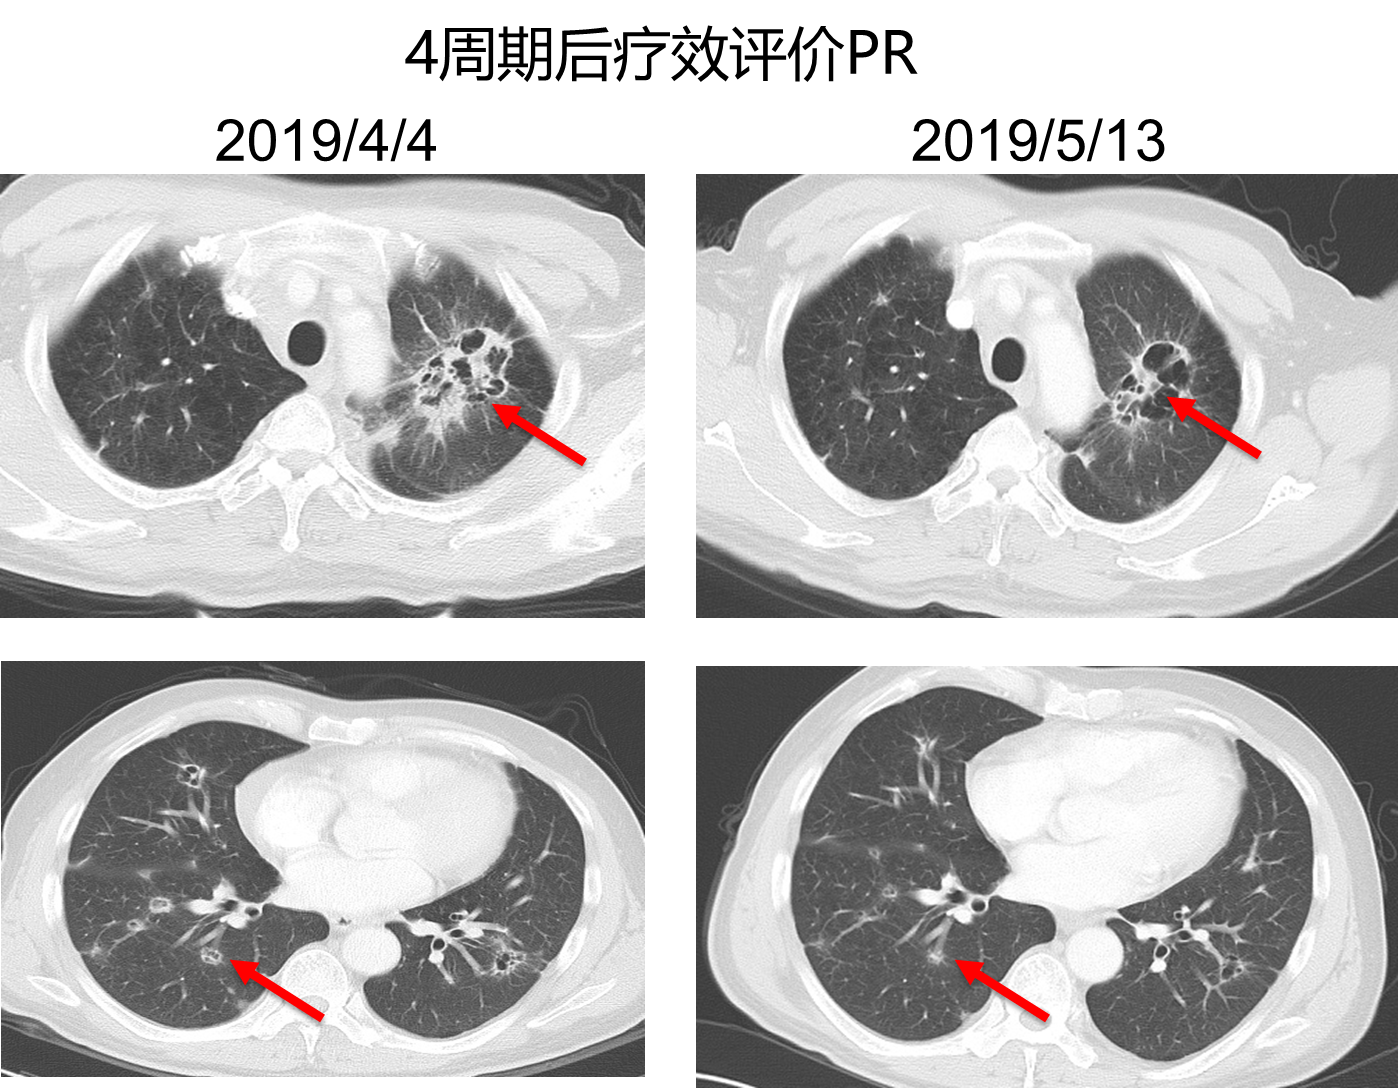

与患者沟通后,综合考虑疗效和性价比,二线治疗选择化疗+免疫治疗,具体方案为:白蛋白紫杉醇 200mg d1、d8+顺铂 40mg d1-3、信迪利单抗200mg d1,q3w,治疗2个周期后,复查胸部强化CT,病灶明显缩小,疗效评价结果为PR。治疗4个周期后,复查胸部CT,病灶继续缩小,疗效评价结果为维持PR。目前患者已经取得疾病缓解7.5月。

图4. 二线化疗+信迪利单抗治疗4周期后复查